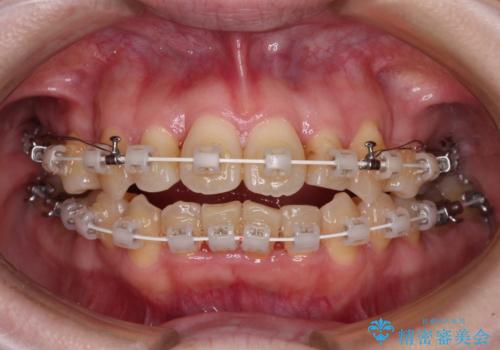

舌の突出癖が強く、治療途中で上下前歯が乖離した開咬となってしまいました。

舌のトレーニングで開咬は改善できますが、なかなかトレーニングが進まず、治療期間は想定よりも長期化してしまいました。